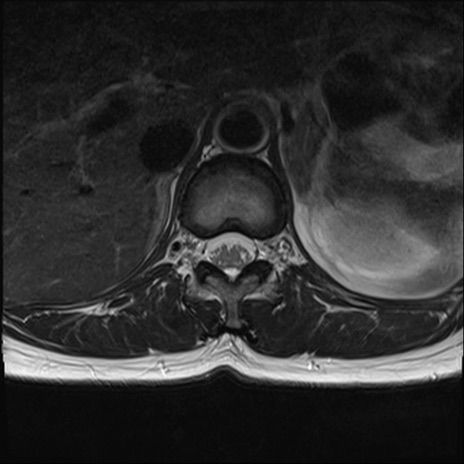

【整形】TIPS症例4 腰椎MRI T2WI(横断像)

腰椎MRI

横断像と矢状断像